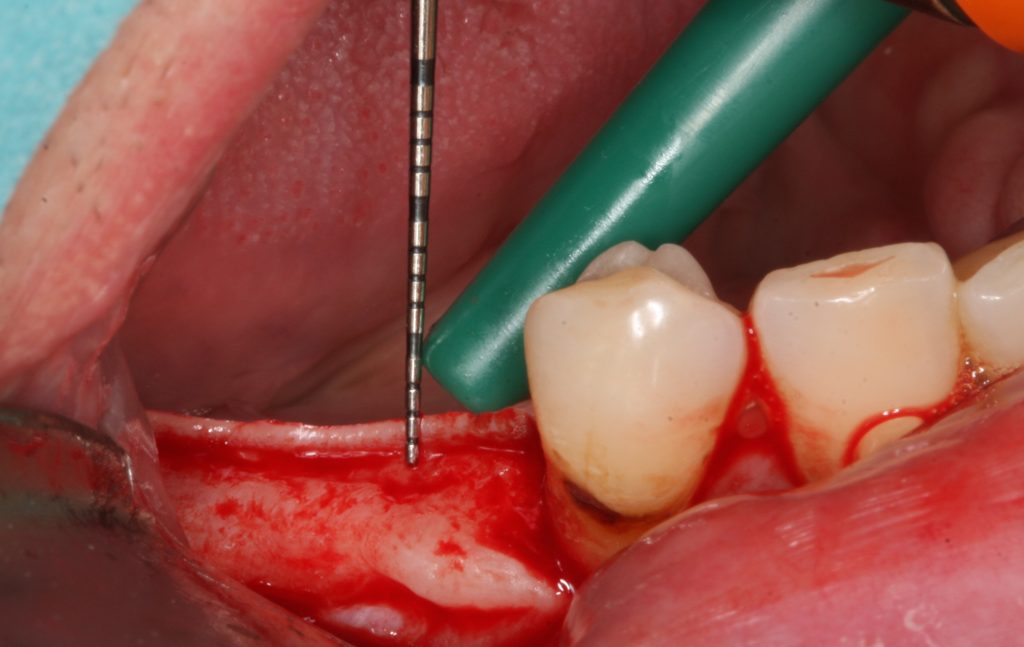

The first thought, which enters the mind, just places implant deeper subcrestally (Fig 5). Firstly, there must be enough place for the alveolar nerve that the implant could be positioned subcrestally in a safe manner.

It is advised that the implant would stop at least 1 mm over the nerve. Subcrestal placement is suggested to cause controlled bone remodeling, but not a bone loss. It is interesting to note, that not all implants can be placed subcrestally. In addition, implant-abutment connection stability becomes very important, if located subcrestally.